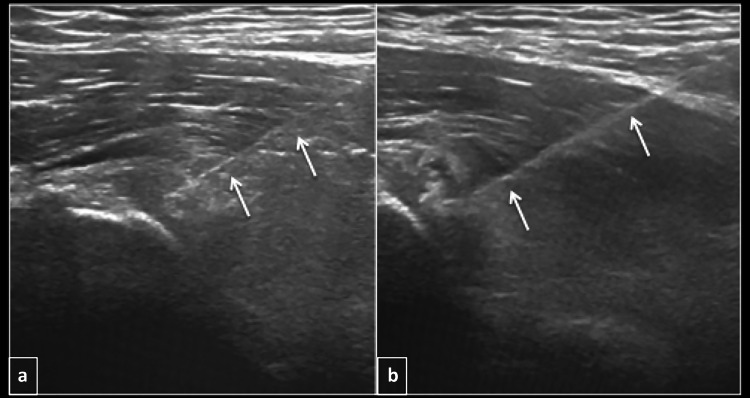

Fig. 4.

Longitudinal ultrasound (a and b) showing needle (arrows) within the calcification during barbotage